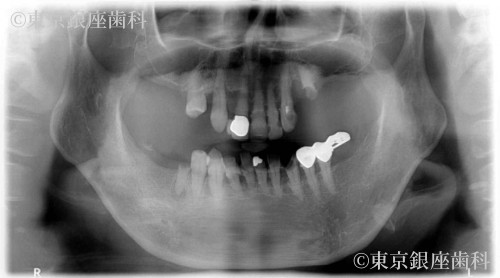

歯周病とむし歯によって咬合崩壊 上下ワンデイインプラントにて再構築した症例

After

歯周病の進行で歯に動揺があり長期の保存が難しく、臼歯の欠損で咬み合わせが下がって前歯部への負担が大きくなっているため全顎的な治療が必要と判断。最小限のインプラント埋入によって咬合を回復させるため上下ワンデイインプラント処置を計画。

ワンデイインプラント治療で審美性、機能、噛み合わせの高さを同時に解決。また歯周病の影響なのか、OPE前は常に赤ら顔で両ほほに炎症が見受けられたがOPE後改善。術後、歯牙の形態や発音等に不具合を訴えていたが最終補綴物装着時には改善。現在半年メンテナンス。特に問題なし。